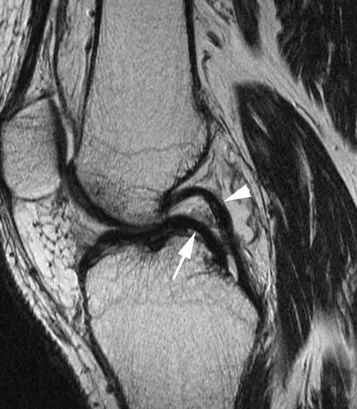

La constatation la plus fréquente est la visualisation directe des fragments migrant dans la région intercondylienne : le repère du 'double ligament croisé postérieur (PCL)' est caractéristique lorsque le ménisque médial est lésé et que le ligament croisé antérieur est intact.Le segment disloqué apparaît comme une bande arquée hypointense parallèle au ligament croisé postérieur normal, produisant un aspect de 'double PCL' (Fig. 7).Des cornes de râteau excessives (plus de 6 mm de taille) peuvent également refléter la présence d'une poignée de baril (Figure 8).Dans ce cas, le fragment de ménisque disloqué est attaché à la corne antérieure saine.

Figure 7 L'aspect de la poignée du ménisque médial présente un signe 'double PCL'.Vue sagittale pondérée PD avec suppression de graisse : le fragment de ménisque disloqué (flèche) se trouve sous le PCL normal (flèche) et forme l'aspect caractéristique 'double PCL'.

Figure 8 Aspect de la corne géante avant.Vue sagittale pondérée en densité de protons.La partie antérieure du fragment luxé (flèche) est rattachée à l'angle antérieur du ménisque (flèche).Notez que les coins arrière ne sont pas représentés (*).